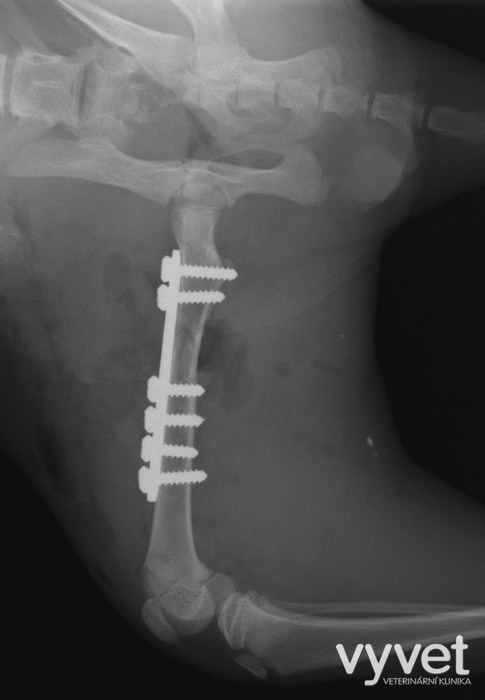

Nejčastějším problémem dlouhých kostí jsou zlomeniny (fraktury)

Rozdělujeme je do několika skupin podle charakteru, množství fragmentů, průběhu linie lomu, dislokace, stability atd.

Je mnoho popsaných metod fixací fraktur. Neinvazivní metodou je přikládání fixačních obvazů a kastů. Tento typ fixace však není ideální, protože nejsme schopni u zvířat zabezpečit dostatečně dlouhou dobu klidu pro srůst kosti. Ideální metodou je invazivnější přístup a to chirurgická repozice s následnou fixací osteosyntetickým materiálem.

Na našem pracovišti používáme zejména ploténky a hřeby.